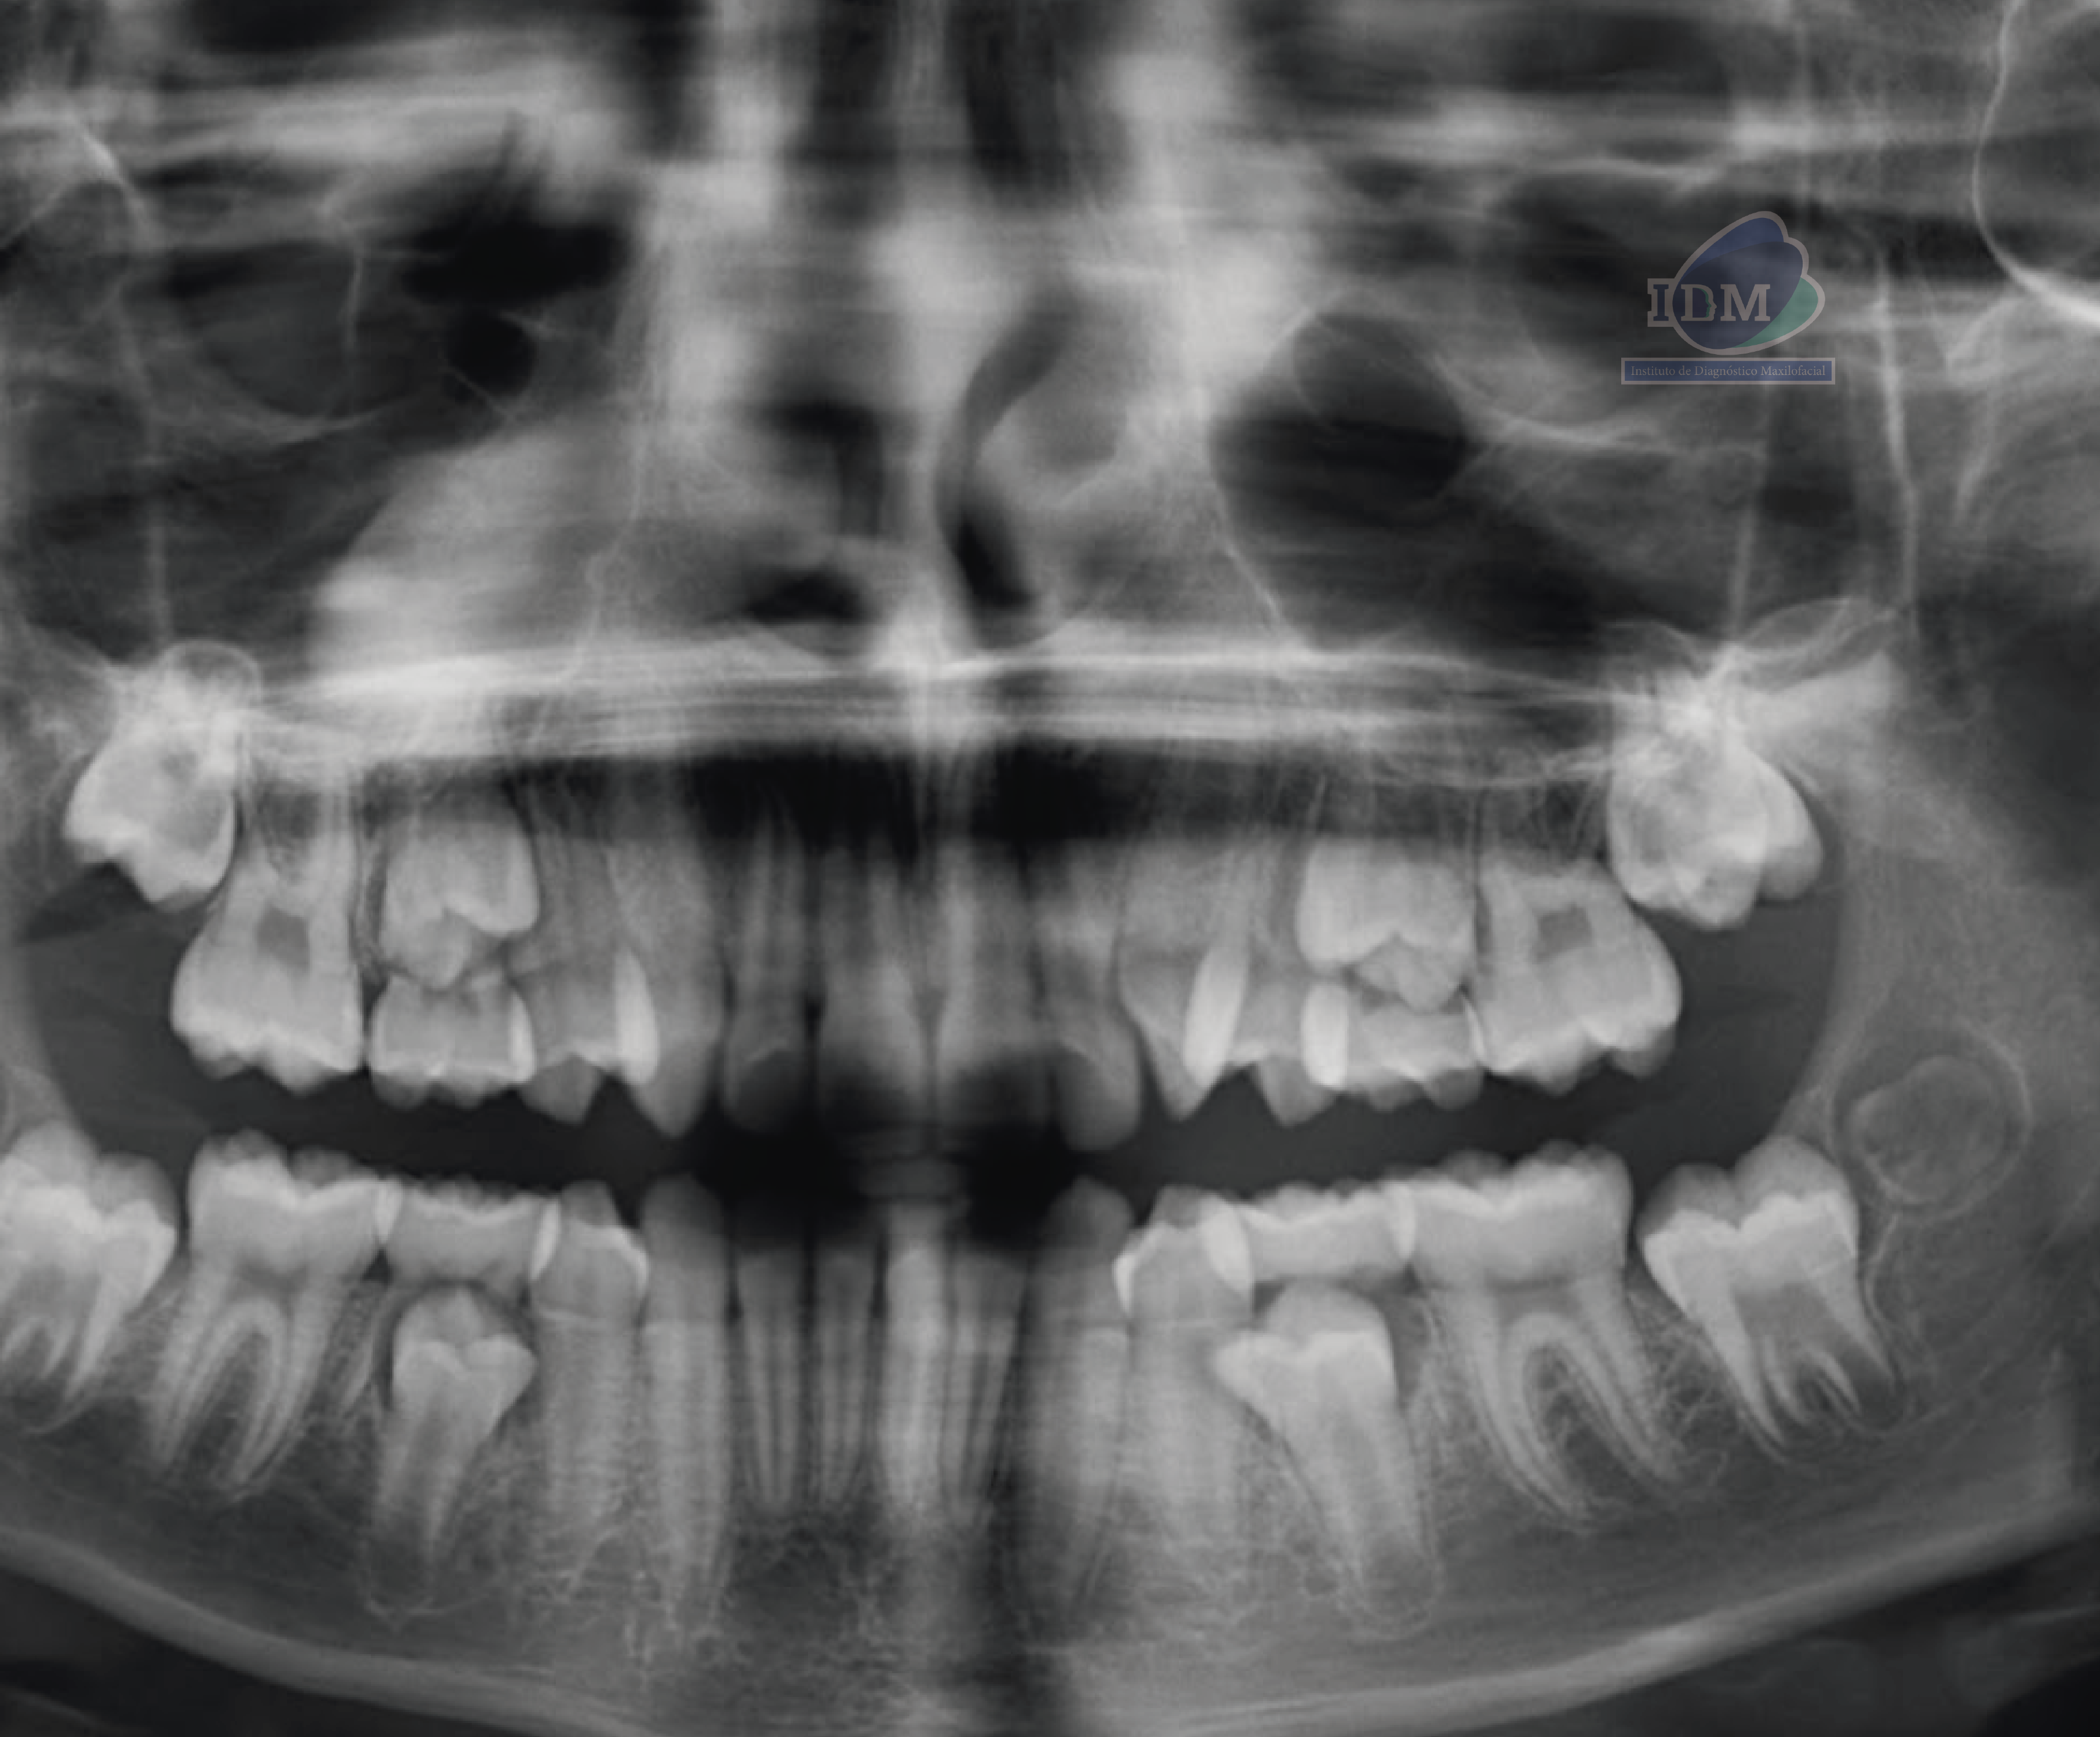

En la radiografía panorámica (Figura 1), se aprecia opacificación de seno maxilar derecho.

Radiografia Panorámica